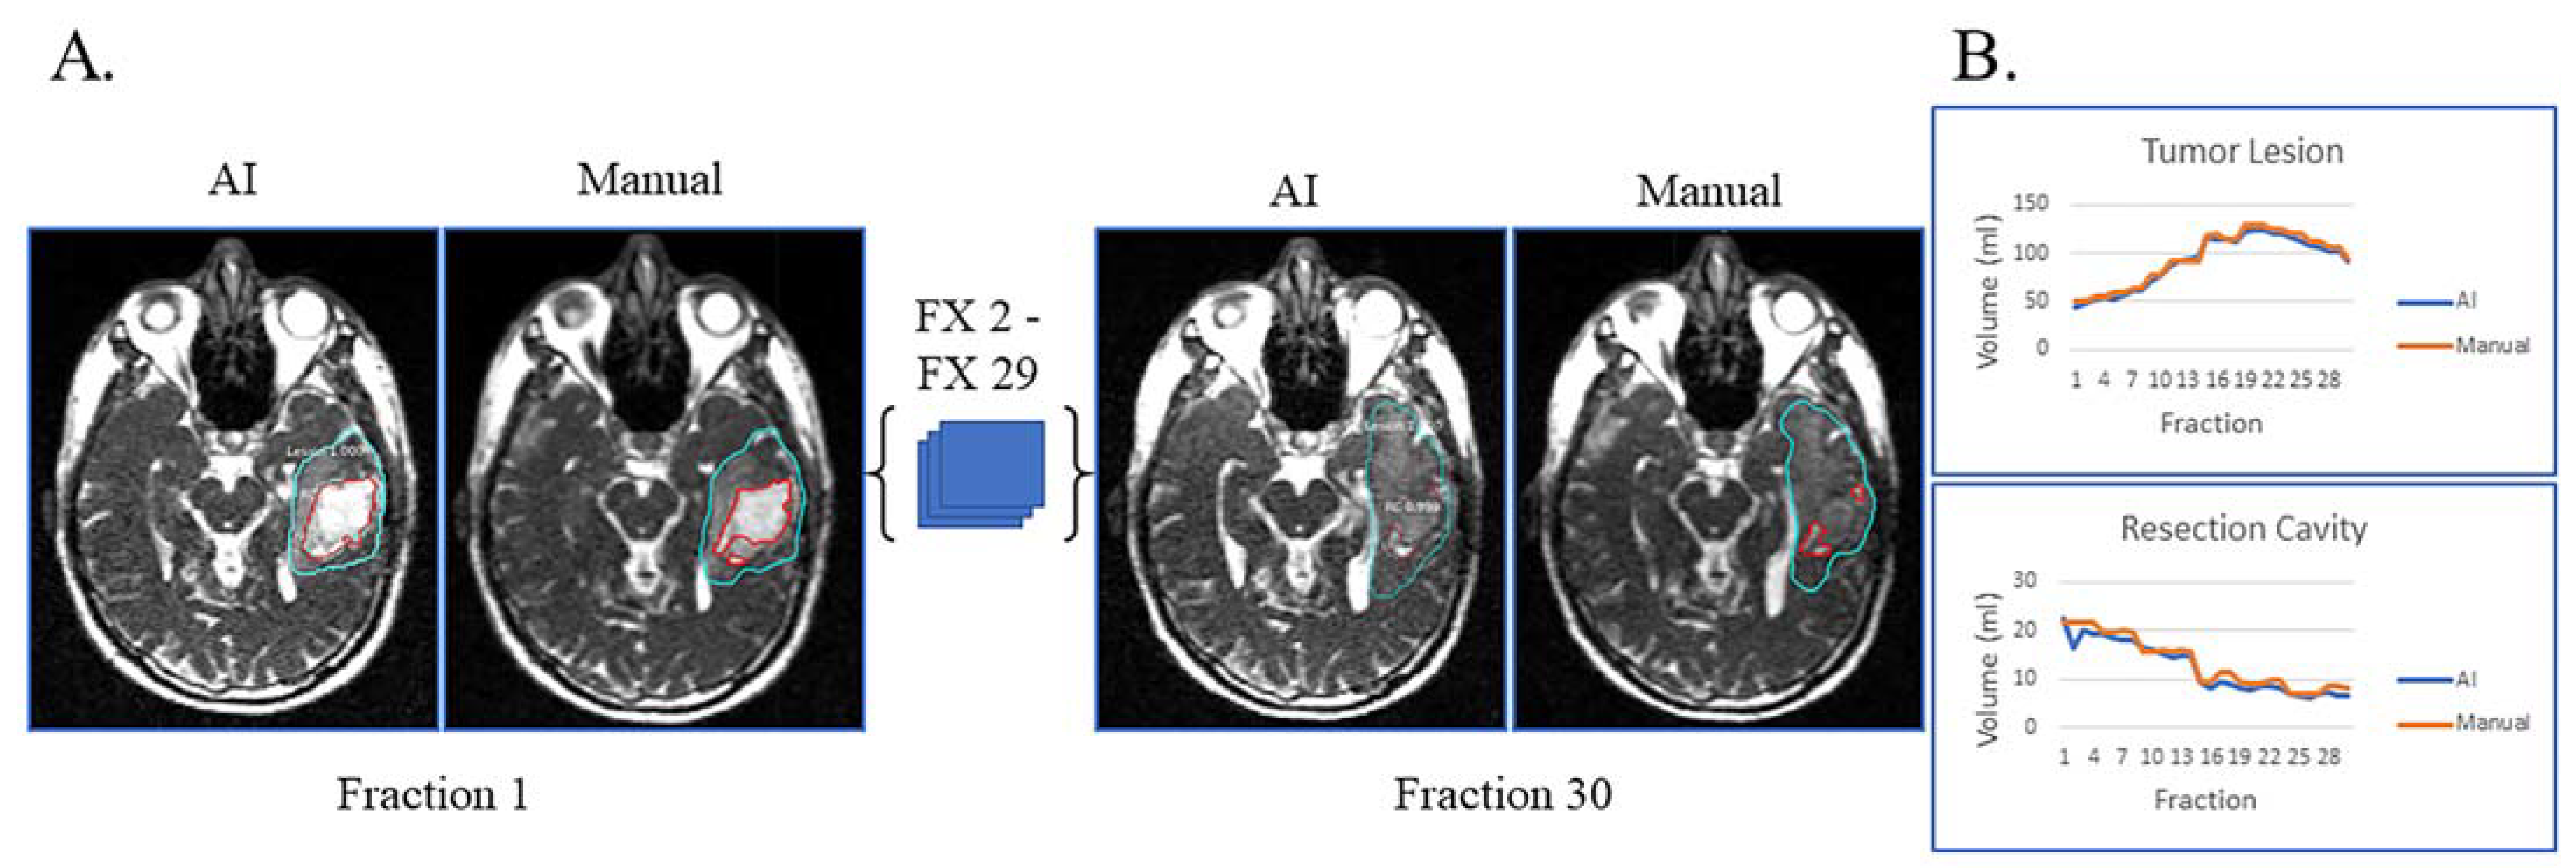

3. Results